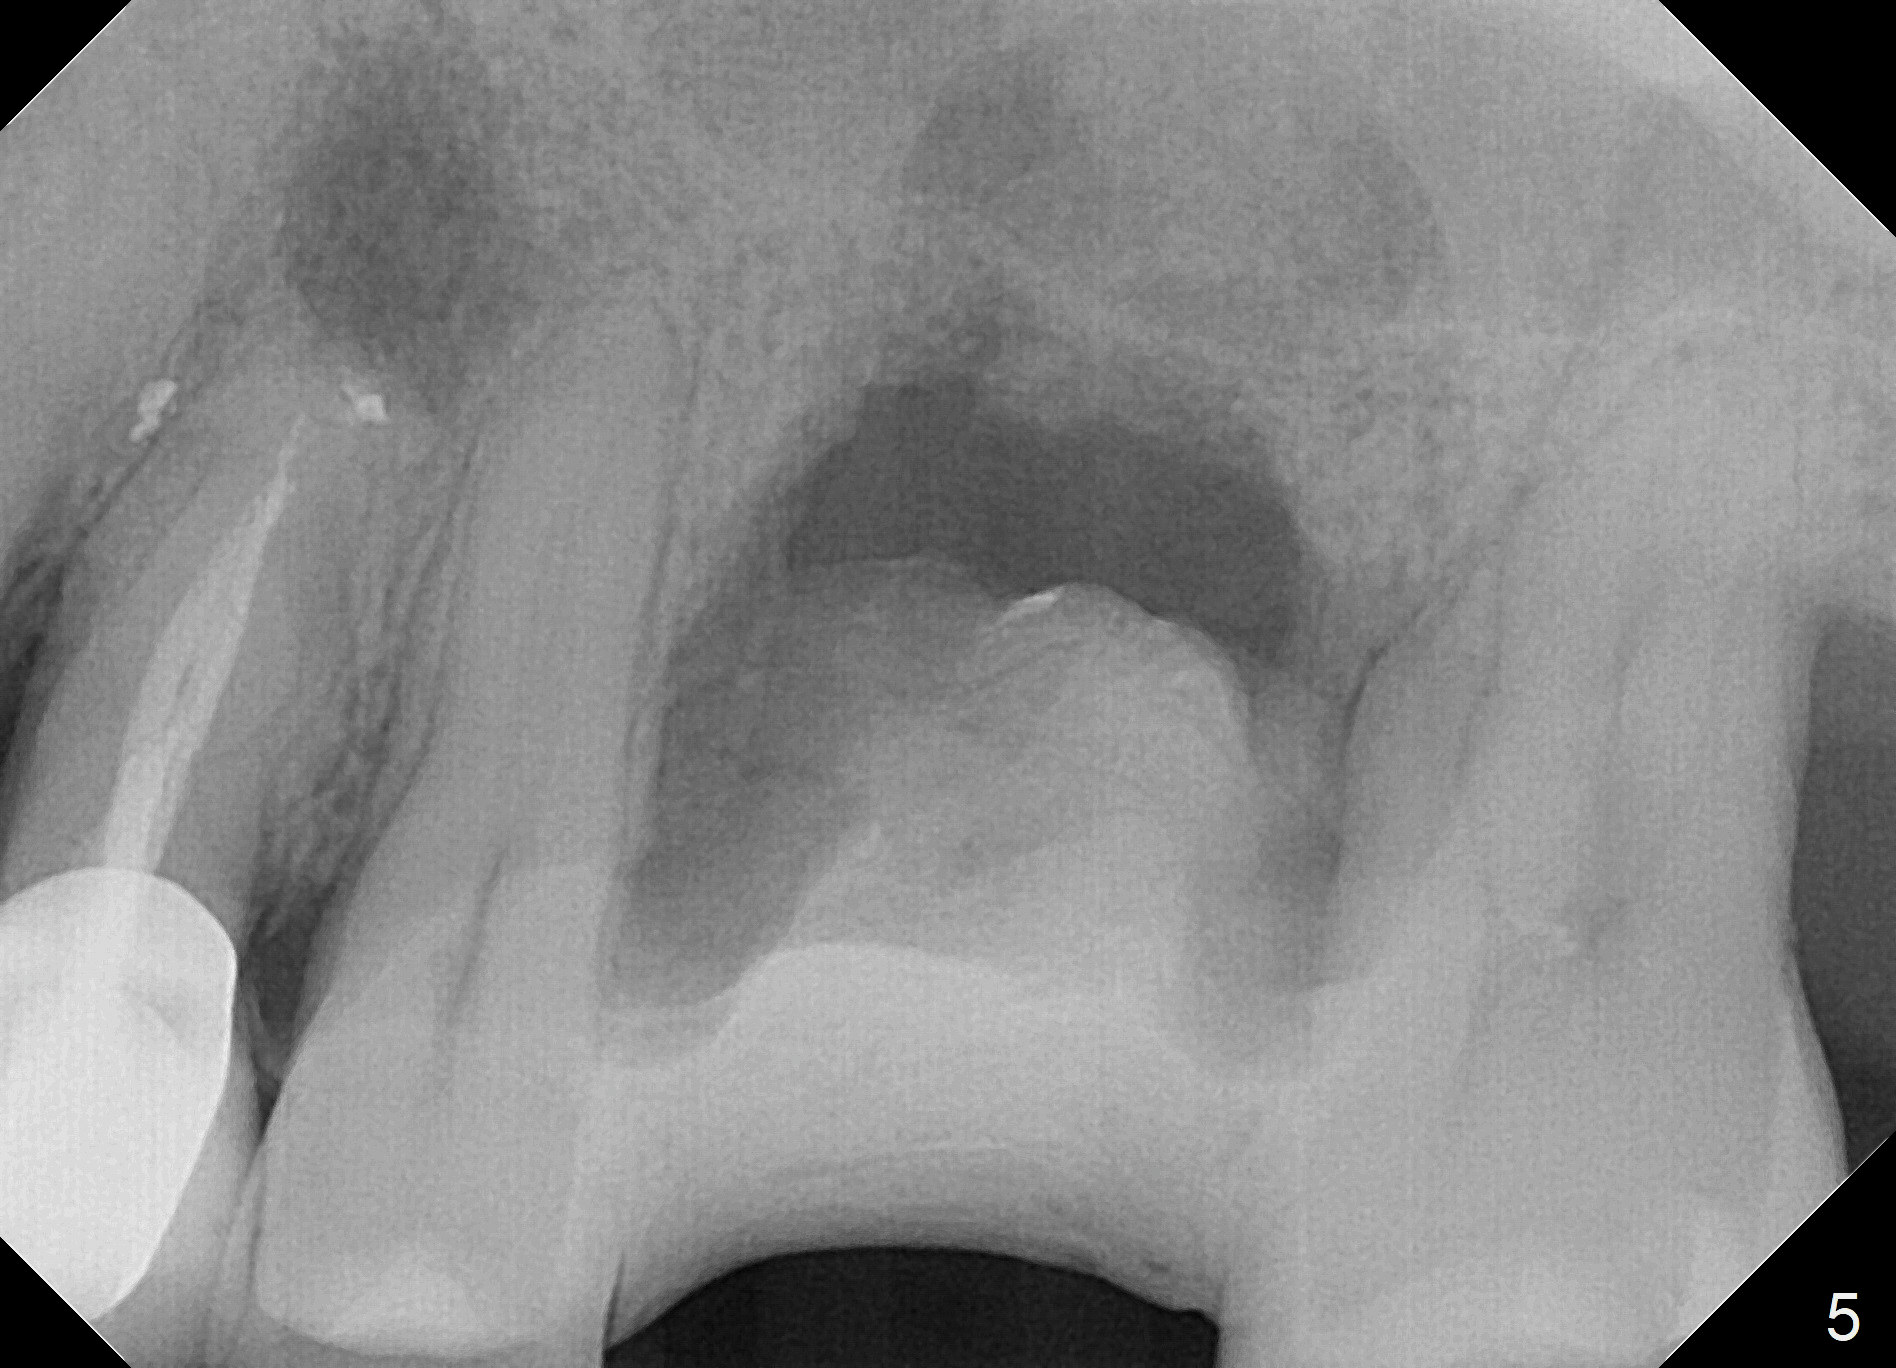

When the tooth #14 is extracted, the buccal plate is lost, while the apex of the palatal socket is perforated.  The palatal slope of the septum appears to be a suitable site for osteotomy, but the depth seems to be 2 mm.  After sequential osteotomy until 5.3 mm with drills, a 5.9 mm SM tap obtains stability (Fig.2).  A 5.9x8 mmm implant is placed with barely sufficient stability after 1 piece of PRF membrane and VeraGraft (Fig.2-4).  The implant rotates and dislodges when an abutment is being placed.  Neither do 6-8x17 mm Tatum taps achieve primary stability.  Socket preservation is performed, followed by periodontal dressing (Fig.5).  Primary stability might have been obtained if a smaller IBS implant with fins were placed in the palatal socket.  The periodontal dressing has dislodged 1 week postop; the socket appears healing (Fig.6,7).  Bone graft seems to be minimal or bone density of the graft is low (Fig.8).  The socket heals with a wide ridge 2 months post socket preservation, but the tooth #15 seems to be buccal (Fig.9) and mesial (Fig.10) shift.  After use of Magic Split and Expanders (until 3.8 mm for 13 mm), try 5 mm dummy implant (Fig.11).  If 6 mm one fails to achieve stability substantially, switch to 7 mm Tatum tapered tap provided there is enough mesiodistal space (use 8 mm implant positioner to gauze the space beforehand (preop)).  Consider using Vanilla (not Vera) Graft to fill in the gap between implant and osteotomy.  When primary stability is obtained, place a nonfunctional provisional to prevent further shifting (Fig.11 white outline).  After osteointegration, use the provisional (reline and separator) to distalize the tooth #15.